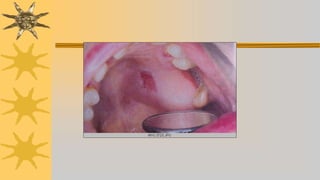

CONTROL DE LA DENTADURA

PARCIAL REMOVIBLE

Primer cita control a 24 – 48 horas de instalado para

corregir cualquier falla o molestia de protesis

Se controla oclusión

Se evaluan tejidos blandos ulceras areas enrogecidas etc

Dolor en frenillos, rebordes

Para detectar posibles zonas de presion ede dentadura sobre

mucosa, se prepara pasta a base de oxido de zink – vaselina y se

pincela parte interna de dentadura

Tambien puede hacerse con silicona fluida

Otros marcan en mucosa inflamada con lapiz y asientan dentadura,

en esta saldrá zona marcada de contacto para hacer desgaste